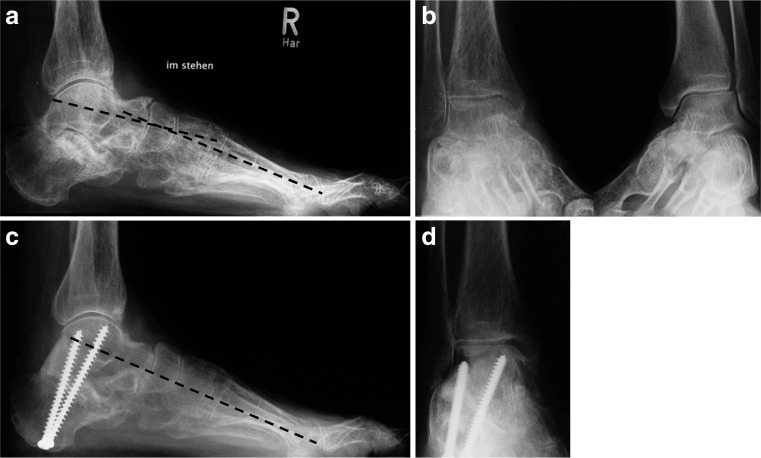

Fig. 4.

a,b Malunited fracture dislocation (Type IV malinion) in a 42 year old female patient one year after a fall from a height. The lateral radiographs reveal loss of height and shortening of the left calcaneus. c The ankle AP radiographs show lateralisation of the calcaneal body with direct deformation of the distal fibula. d CT scanning reveals the exact outline of the former fracture line. e After performing a lateral approach, the direct contact between fibula and calcaneus is seen. The peroneal tendons (held with a soft strap) are typically displaced subcutaneously. f Treatment consists of an oblique osteotomy along the former fracture plane that corrects all aspects of the malunion. g Subtalar fusion is supplemented by bone grafting from lateral (wedge) and screw fixation (h) across the former fracture into the sustentaculum. Additional soft tissue procedures in this case included Achilles tendon lengthening, ankle arthrolysis with lateral debridement and osteophyte excision, and peroneal tendon rerouting. i,k Postoperative radiographs show correction of the calcaneal axis in all three planes and restoration of the talocalcaneal height (double arrow) and talus-first metatarsal axis (interrupted line). l,m Four years later the radiographs show solid union in the corrected position without notable progression of the pre-existing ankle arthritis. Function is widely restored and pain markedly reduced